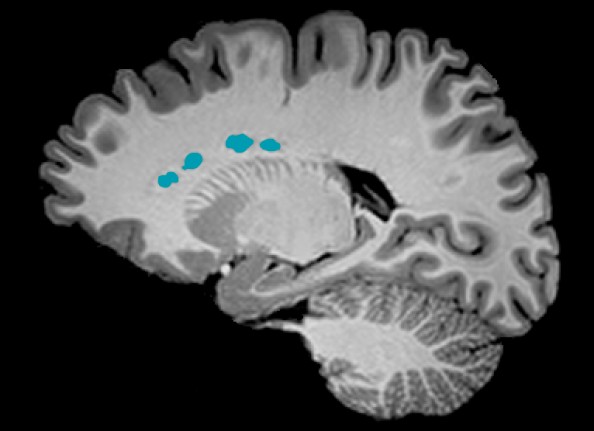

Heterotopi av hjernens grå substans er en bred gruppe migrasjonsforstyrrelser hvor makroskopiske ansamlinger av nevroner befinner seg på feil sted i hjernen (1). Periventrikulær nodulær heterotopi er den vanligste formen og skyldes at ependymale celler tidlig i fosterlivet ikke får satt i gang eller fullført cellevandringen fra ventrikkelgulvet til hjernebarken. Cellene modnes allikevel til nevroner, som blir liggende som knuter av grå substans inni hvit substans nær ventriklene.

Periventrikulær nodulær heterotopi har et bredt spektrum av kliniske presentasjoner, fra fullstendig normal hjernefunksjon og ingen symptomer på sykdom til mental utviklingsforstyrrelse og intraktable fokale epileptiske anfall (1). Tilstanden oppdages ofte tilfeldig ved bildeundersøkelser som er gjort på en annen indikasjon som ikke er relatert til heterotopien. Dette er også tilfelle her: Funnet ble gjort tilfeldig under en avbildningsstudie av normal hjernefunksjon.

Periventrikulær nodulær heterotopi vises ved avbildning på ulike vis (2). Det vanligste er kontinuerlige knuteformede masser umiddelbart i tilknytning til sideventriklene (3), men det kan også vises som på dette bildet: som perler på en snor, innhyllet av hvit substans.